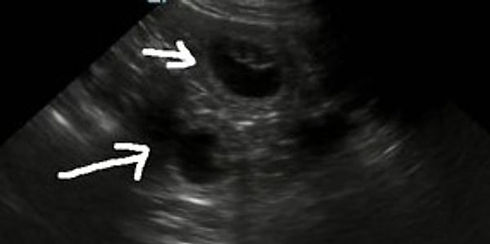

This image is of the uterine horn at 30 days gestation with 10 embryos.

Size of each embryo is about 2 - 3cm.